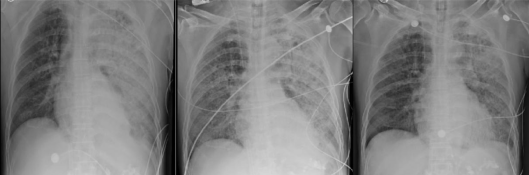

入院后予美罗培南+万古霉素+莫西沙星+更昔洛韦+卡泊芬净经验性抗感染、血浆置换、改善微循环、营养支持、CRRT等治疗。2021年9月3日行EB病毒DNA、巨细胞病毒DNA、G试验、GM试验等检查,同时行支气管镜检查:气道黏膜轻度充血、水肿,隆突锐利,双肺各叶段黏膜充血水肿明显,未见明显出血及糜烂;各叶段开口通畅,未见新生物;各叶段可见中等量稀薄分泌物,留取支气管肺泡灌洗液培养、抗酸染色及NGS等。9月6日NGS结果回报鲍曼不动杆菌(序列数417509)、铜绿假单胞菌(序列数117424),同时肺泡灌洗液培养出多重耐药鲍曼不动杆菌。因考虑患者起病急、免疫力低下,可能存在鲍曼不动杆菌及铜绿假单胞菌混合感染,改用替加环素联合多黏菌素B抗细菌治疗。9月8-10日复查胸片提示双肺渗出较前稍有吸收(图2)、炎症指标下降(图3),但仍需血管活性药物维持,循环情况改善不明显。9月11日家属要求放弃治疗自动出院。

图2 9月4日、8日、10日复查胸片可见左肺渗出较前有所吸收